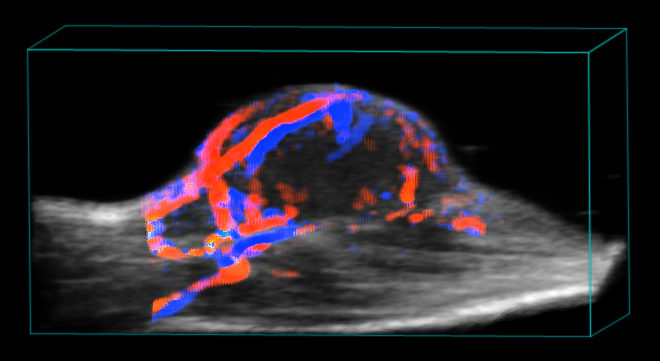

With the 3D Mode you will see the entire shape of your target anatomy on a micrometer scale. 3D Mode allows for measurements of area, height, length and volume of the target anatomy.

Aortic arc

Combining 3D Mode with Color Doppler, Power Doppler, Non-Linear Contrast Mode or Photoacoustics sub-modes makes it possible to extract even more parameters such as depth, volume and percent vascularity, all at a micrometer scale.

Tumor blood supply